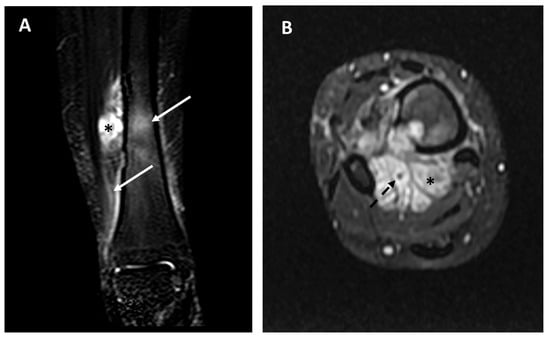

- Tumor extra-skeletal extension in the soft tissues (categorized as: absent, mild [i.e., smaller than the intra-osseous component], moderate [i.e., equal to the intra-osseous component], severe [i.e., larger than the intra-osseous component].

- Relationship/contact with the near major vascular bundles (categorized as absent, near <3 mm, in contact, and vascular encasement), as already performed in previous sarcoma studies [14].

| Extra-intra osseus extension: Intraosseous only (0), intra- and extra-osseous (1) | Intraosseous only (14), Extra-osseous (2) | Intraosseous only (0), extra-osseous (6) | 0.0004 * |

| Vascular invasion: No vascular contact (0), Vascular contact or encasement (1) | No vascular invasion (16), Vascular invasion (0) | No vascular invasion (1), Vascular invasion (5) | 0.0002 * |

| Extra-intra osseus extension: Intraosseous only (0), intra and extra-osseous (1) | Intraosseous only (14), Extra-osseous (2) | Intraosseous only (0), extra-osseous (6) | 75.40 (3.15 to 1802.71) | 0.01 * |

| Vascular invasion: No vascular contact (0), Vascular contact or encasement (1) | No vascular invasion (16), Vascular invasion (0) | Novascular invasion (5), Vascular invasion (1) | 121.00 (4.28 to 3424.73) | 0.01 * |